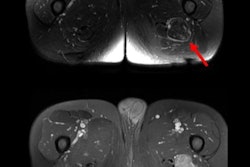

Examples of volumetric segmentation in three different patients. Volumetric segmentations of D-TGCT performed with Brainlab software on sagittal T1 SPIR-weighted sequences post gadolinium. (A) tumor is segmented in the posterior cruciate ligament (PCL) recess (volume shown in red). Volume = 3.8 cm3. (B) Tumor segmentation in anterior, middle, and posterior compartments. Volume = 86.2 cm3. (C) Tumor segmentation of a case with marked posterior disease, present in the PCL recess, subgastrocnemius synovial recesses, Baker's cyst, and extending extra-articular in the popliteal fossa. Volume = 91.9 cm3. Figures courtesy of Dr. Geert Spierenburg, Dr. Kirsten van Langevelde, et al and Insights into Imaging."3D segmentation is not part of our standard diagnostics -- this was done as a pilot study, in a research setting," first author Geert Spierenburg (trainee orthopedic surgeon) and senior author Dr. Kirsten van Langevelde (musculoskeletal radiologist) told AuntMinnieEurope.com in an email. "We find that using RECIST for tumor response assessment is just not a useful method for these diffusely growing synovial tumors."